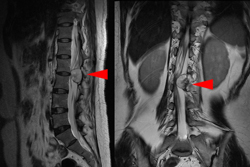

图3-1,CT矢状面和冠状面重建,显示病变为成骨性,病变内有点状钙化。

图3-2,CT横断面显示病变累及L2-L3水平椎骨。

图3-3,MRI矢状面及冠状面显示病变侵入椎管明显压迫硬膜囊和马尾神经

图3-4,MRI横断面显示病变存在软组织成分,在左侧L2-3椎间孔区肿瘤累及椎管内外,明显压迫马尾神经,并且包绕左侧L2神经根。